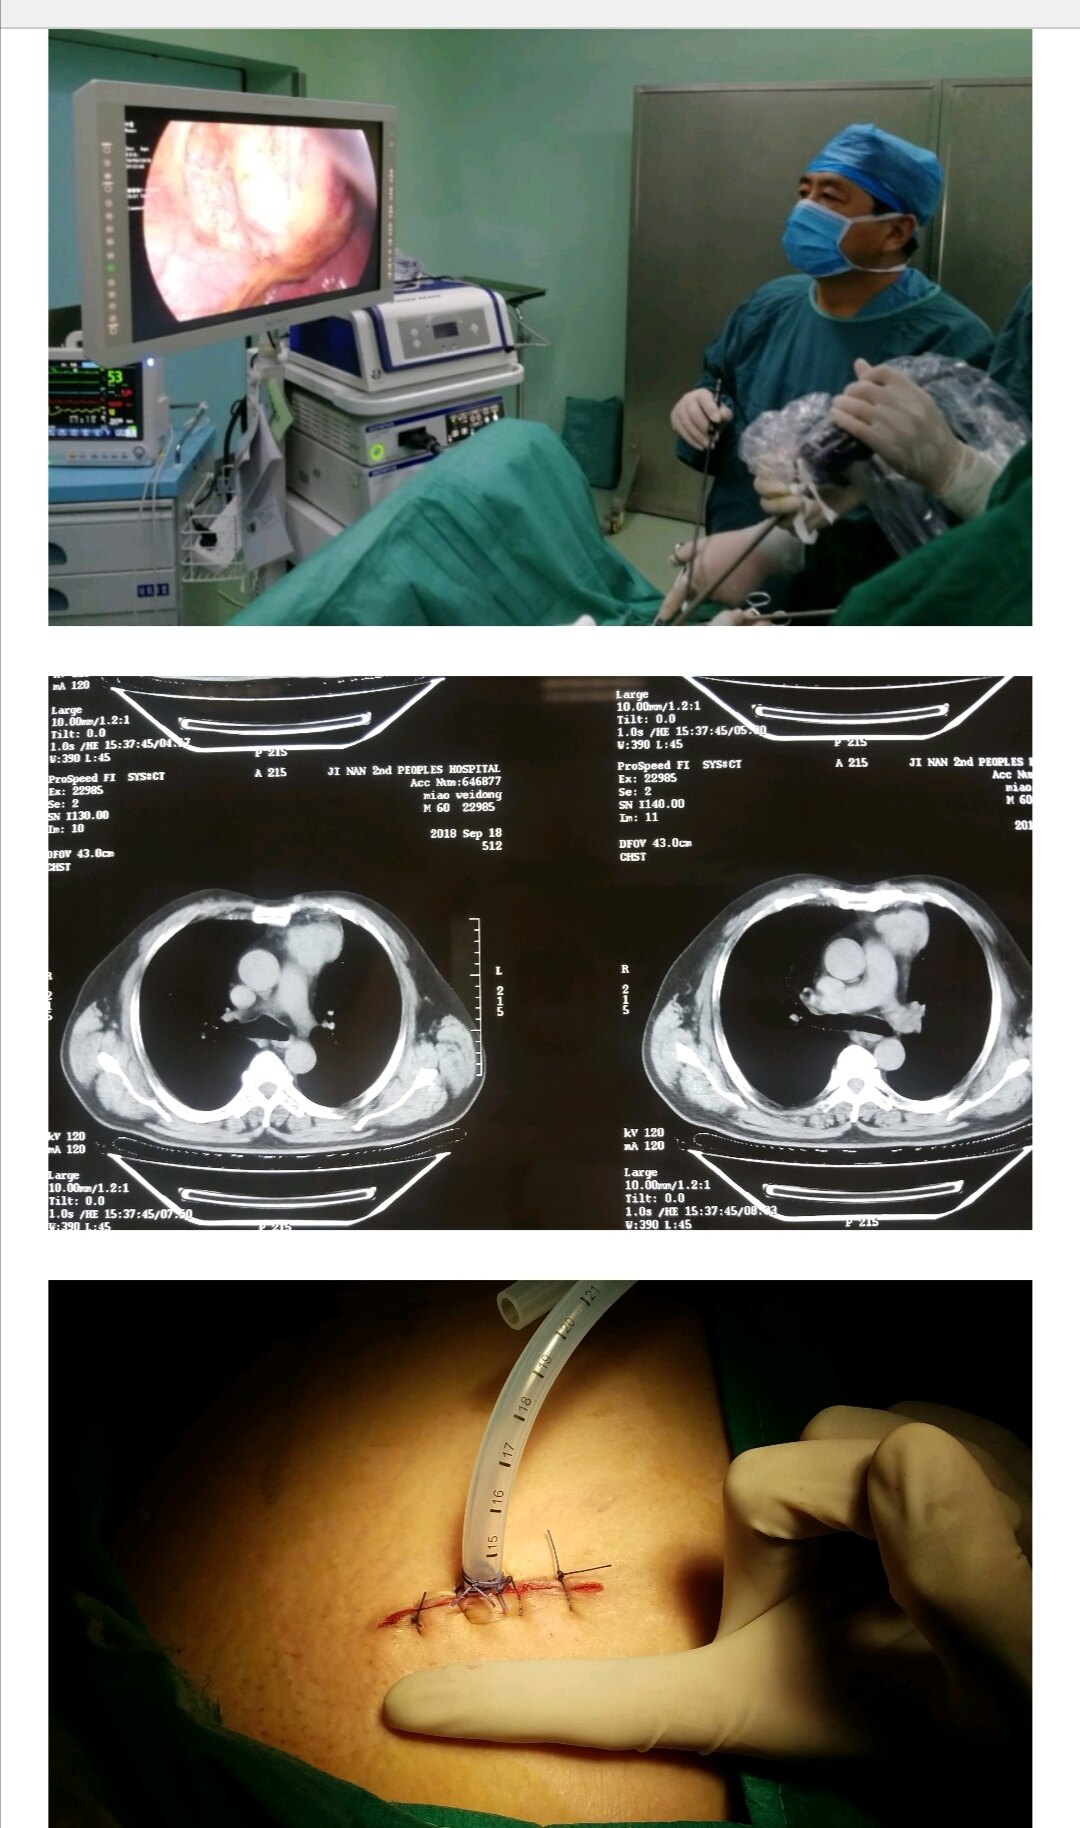

我:关于盆腔阻塞的问题,胸腔镜检测是金标准的确诊根据。仍然以来,我就比较主张怀疑输精管阻塞的女生直接选择做胸腔镜检测,尽管手册不那么建议,并且我个人比较倾向这些方法。我的理由比较粗鲁,胸腔镜检测是个金标准,盆腔究竟通不通,胸腔镜能看得最清楚,胸腔镜还能把挛缩直接分开,盆腔假如积水同时就把放疗做了。胸腔镜看见输精管是通的,那确实就是通的,而且能确认通畅而无挛缩。胸腔镜能够发觉一些没意料到的问题,例如有的人可能存在初期的卵巢内膜异位症或则子宫肌瘤等。

并且选择直接做胸腔镜放疗也是存在问题的,哪些问题呢?第一,放疗费用高,这大约是中国人最无法接受的现实,尤其是受孕困难户,好多受孕困难户虽然并不富裕。他们常常为怀女儿的事情四处奔忙寻医,工作挣钱也荒废了。第二,这显然是个放疗输卵管造影大概费用多少钱,放疗都是有外伤的,都是有风险的,无论机率多少,这个放疗还要局麻,麻醉也是有风险的,尤其是局麻,麻醉风险还可能是致命性的,无论机率有多低。这大约是我们大夫最在乎的问题。第三,从总的社会经济学层面考虑,也就是算算所有弱精症男性就诊的总费用,若果全都直接做胸腔镜,肯定要多花出去不少钱,而且假如把盆腔活检置于后面,作为第一步筛查手段,能把好多盆腔很通畅的女人给筛出去,防止胸腔镜放疗,这就为社会省下很大一笔费用。但对于某个人而言,她可能更在乎的是大夫能给出一就是一,二就是二的明晰推论。但是,盆腔活检未必能给出这样的推论,由于活检结果显示通畅的妇女,说不定有某些鼻窦还是有挛缩的,盆腔其实通畅,有时侯输精管和子宫未必在一起,中间可能隔著挛缩带,还有的即使没有挛缩,没准还有其他子宫诱因导致弱精,例如卵巢内膜异位症,这种都只有胸腔镜能发觉得了。其实,这不部份人极某些,即便输精管活检显示通畅的女人,子宫内尚且情况都是好的。而对于输精管活检显示阻塞的女人而言,这就不省钱来,由于接出来须要做胸腔镜放疗明晰阻塞情况、部位、是否有机会放疗解决等问题。而对于报告说“通而不畅”、“粘连上举”、“欠通畅”等描述性语言的,就让大夫操蛋了。这特么究竟跟患者说是通畅还是不通畅啊?所以这类患者也是须要做胸腔镜明晰的。

做试管小孩之前,是有必要做个胸腔镜的。理由有三:第一,胸腔镜能更清楚了解卵巢的情况;你如何晓得一定是输精管阻塞?你如何晓得你就只有输精管阻塞,万一不是呢?第二,胸腔镜放疗,其实能额外提供一次自然受精的机会。放疗还没做,你如何晓得你就一定不能自然受孕?没试过谁晓得,问大夫?你以为大夫是神仙还是神棍?第三,子宫状况确实糟糕,盆腔惨不忍睹,下定决心做试管的人,最好先结扎输精管,在做试管宝宝。输精管完全不通的人,难以自然受孕,连怀死胎都没机会(怀流产的前提是输精管要通,但未必“畅”)。而且假如做试管小孩,你不但有机会怀宫内孕,也有机会怀流产。做试管作出流产的事情并不稀奇。